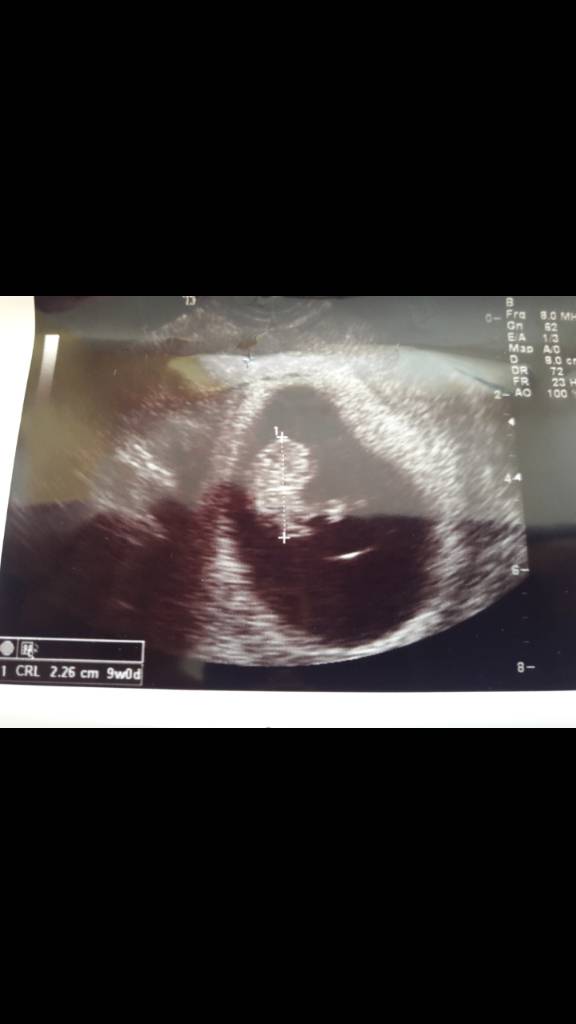

Cudownosci ❤❤A tak dzisiaj wyglądają moje maleństwa. Jeden wyprzedza w swoim rozwoju o 3 dni. [emoji7]Zobacz załącznik 881319Zobacz załącznik 881320

Dzisiaj równo 9 tygodni. Ale z usg jeden maluch wychodzi na 9t3d a drugi idealnie na 9t0d.Justynko który to tydzień?

A tak dzisiaj wyglądają moje maleństwa. Jeden wyprzedza w swoim rozwoju o 3 dni. [emoji7]Zobacz załącznik 881319Zobacz załącznik 881320